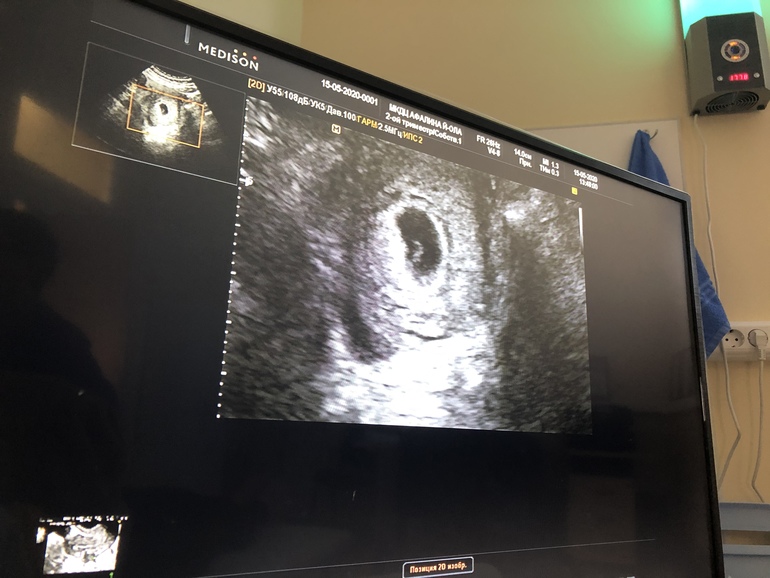

15 мая было решено топать на узи! С первой же секундочки у врача не было сомнений и даже не пришлось смотреть изнутри, все хорошенько видно уже по поверхности животика!

Вот он наш малышок! Маленькая неожидонная бусинка замечательно сидит прямо по центру

Размеры 19,5*5,4*12,2мм что соответствует 5,4 недели беременности!